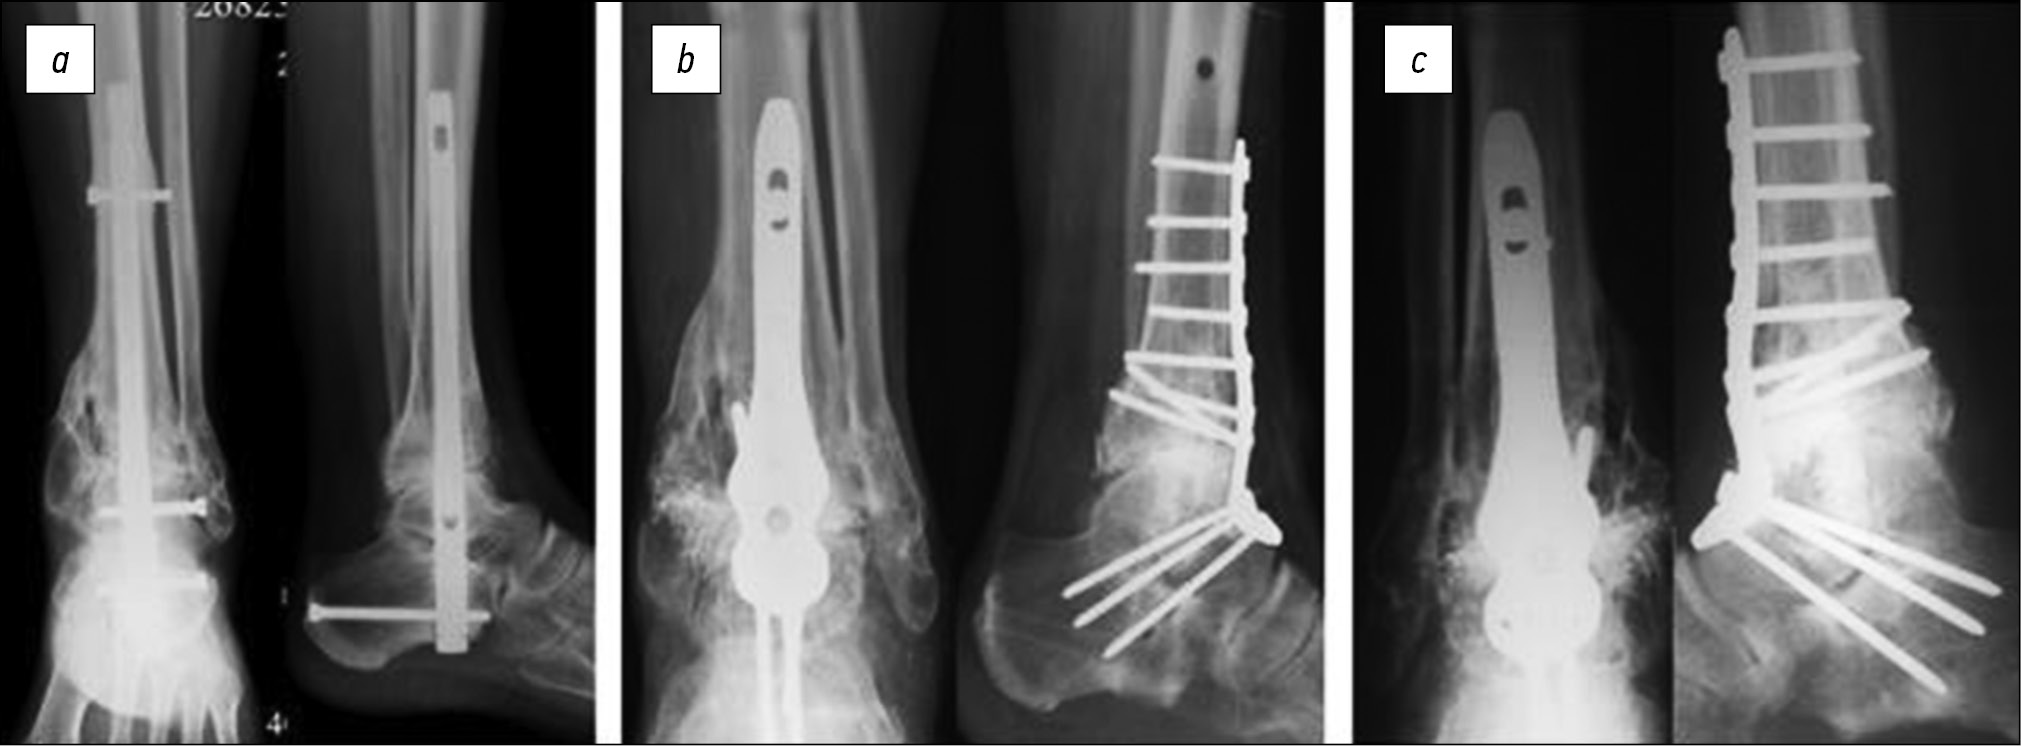

Больная Р., 45 лет, госпитализирована повторно через 8 месяцев после выполнения первичной операции. Клинико-рентгенологическое обследование показало несостоятельность фиксации в связи с переломом металлоконструкции, наличие диастаза между таранной и большеберцовой костями, дефекта купола таранной кости, вальгусной деформации стопы. В ходе ревизионного вмешательства выполнены удаление интрамедуллярного стержня и блокирующих винтов, моделирующая резекция суставных поверхностей таранной и большеберцовой кости, устранение деформации, замещение дефекта купола таранной кости путём перемещения переднего края большеберцовой кости, реостеосинтез накостной пластиной с угловой стабильностью винтов (рис. 3).

Рис. 3. Рентгенограммы больной Р.: a — через 8 месяцев после первичного оперативного вмешательства, b — после ревизионного оперативного вмешательства, c — через 6 месяцев после ревизионного оперативного вмешательства

Fig. 3. Radiographs of patient R.: a — 8 months after her first surgery, b — the revision surgery, and c — 6 months after the revision surgery